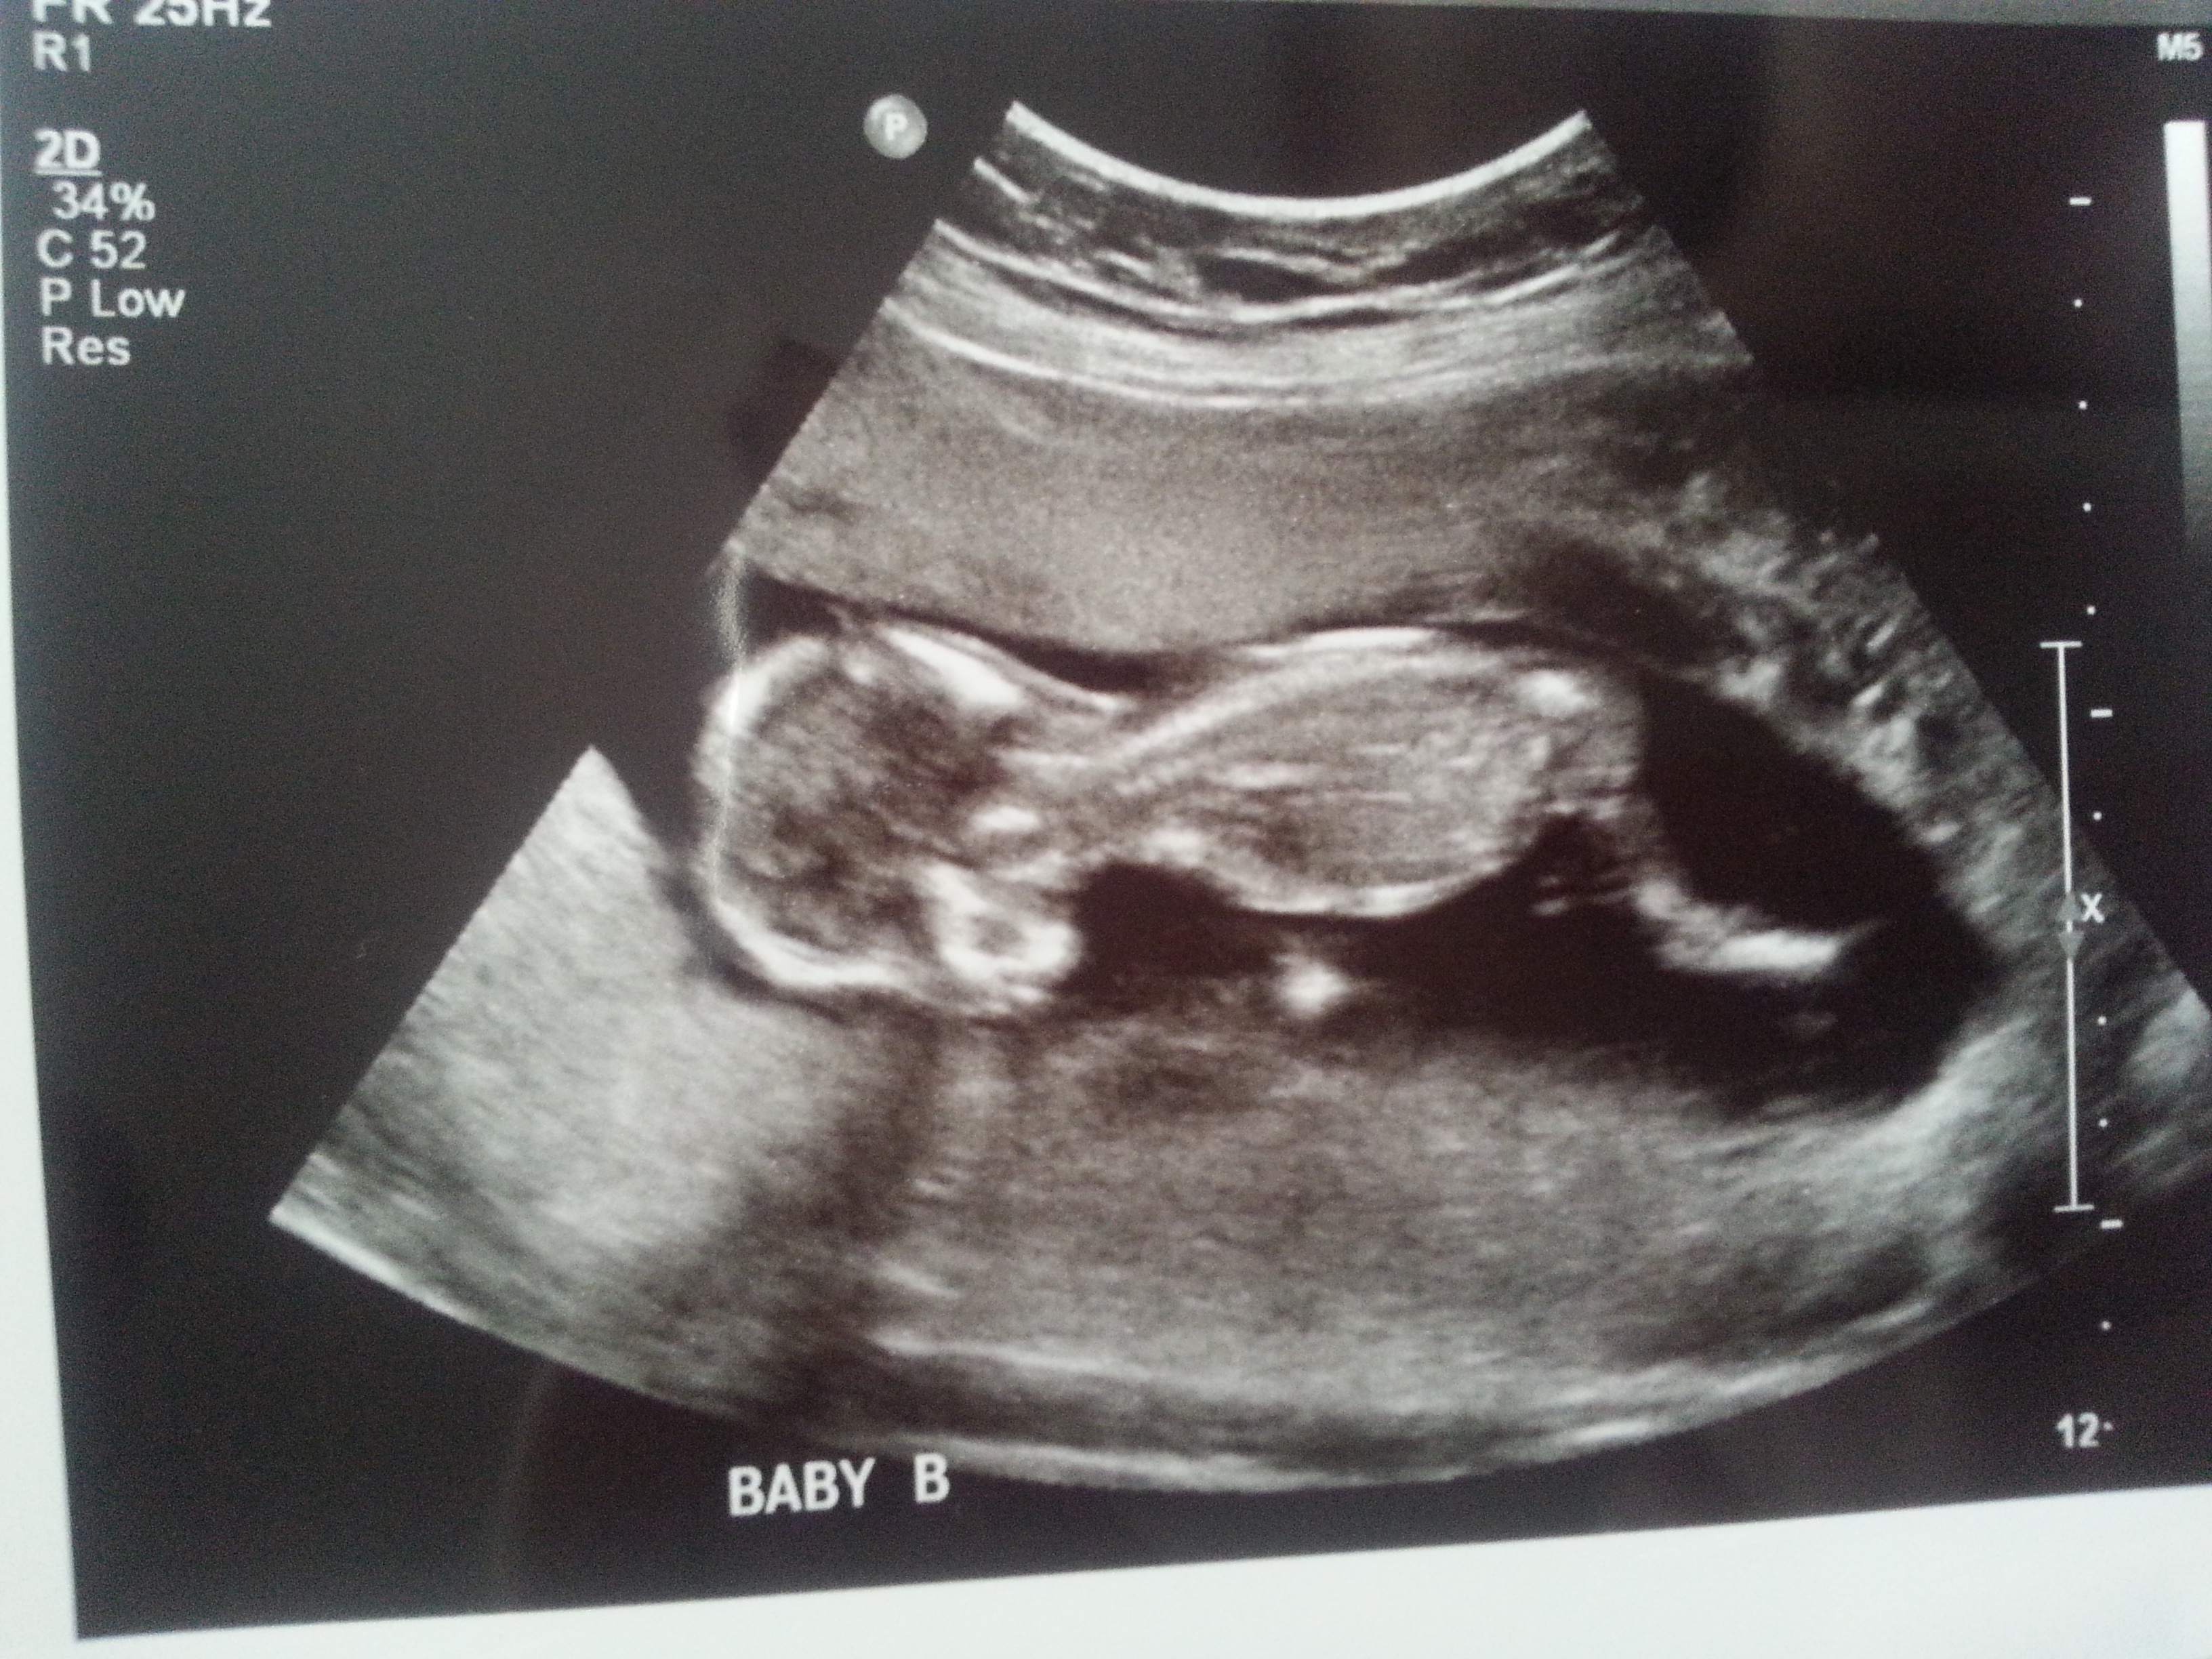

I was 12weeks 6 days and measuring 13weeks 3 days.

Maybe boy/girl. Not the best shots though!

I think B is a boy and A is a girl.

I think B is def a boy. A has a boyish skull but girly nub. I'd go with the nub though and lean girl! Congrats on your twins!